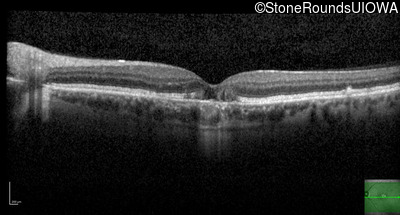

Optical Coherence Tomography - Left - 20/40 +1

Exemplar / OCT Stack